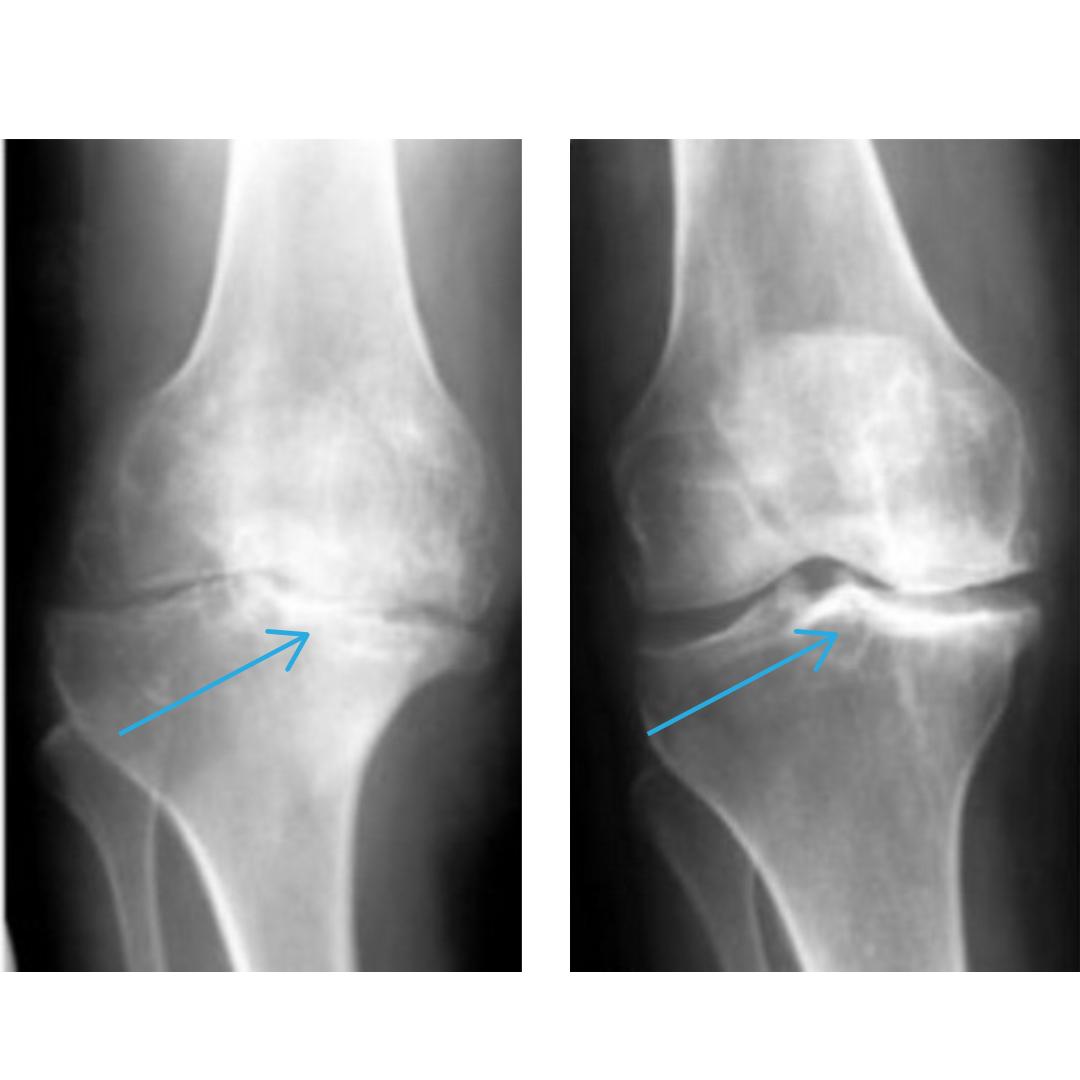

«Хвороби опорно-рухового апарату – посідають перше місце серед хвороб, що призводять до інвалідності та навіть смерті. За статистикою, 94% артритів та артрозів виникають через надлишкові сольові відкладенння у суглобах. У 89% випадків, пацієнти, які страждають на хвороби суглобів закінчують в інвалідному візку, а згодом і смертю.